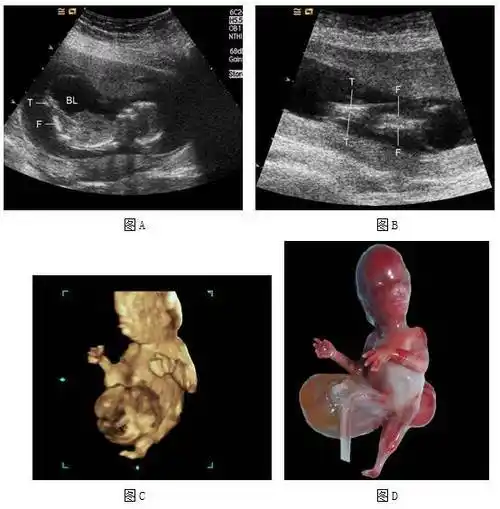

胎儿严重结构畸形的产前筛查与诊断:从中孕期提前到早孕期